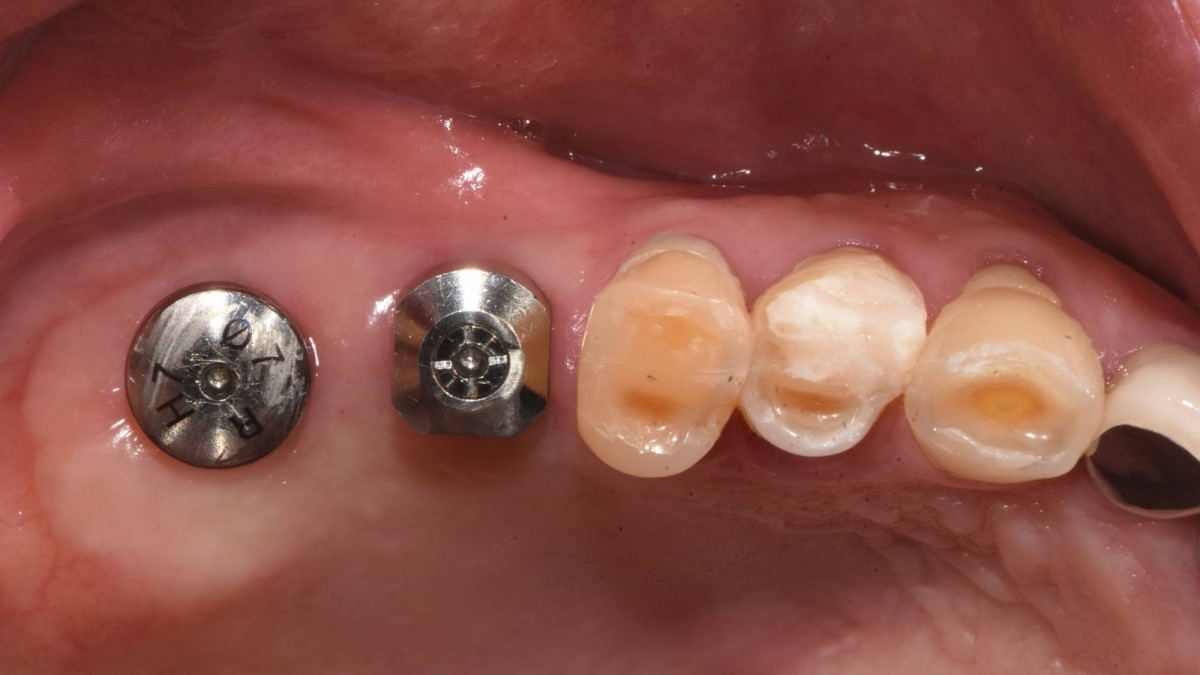

Socket Lift and Implant Placement in the right maxilla.

<GCacg> A 56-year-old male patient complained of pain in the right upper and lower jaws. And he wanted the upper first molar to be pulled out first.